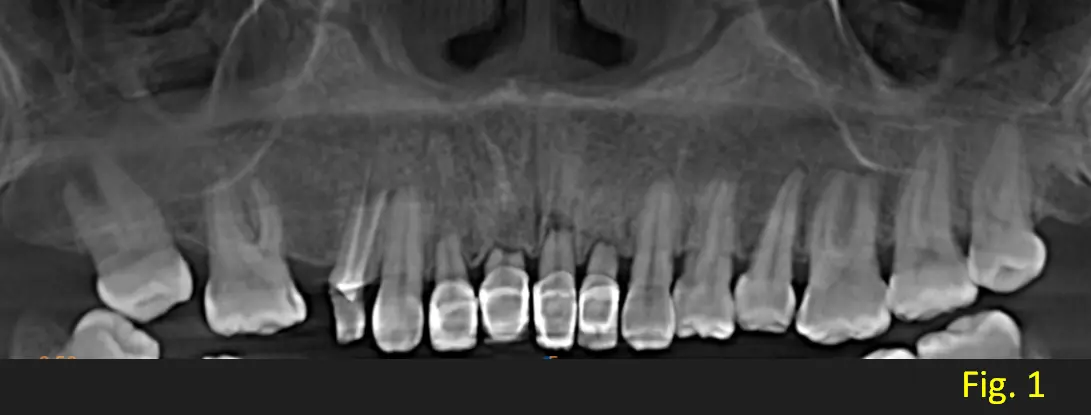

En una vista panoramica se observa que los apices de los incisivos centrales y laterales presentan una forma redondeada y corta. Pieza dentaria 2.1 presenta proceso de reabosción debido a que sigue con los patrones rectos y marcados como podemos visualizar en los cortes transaxiales (ver Fig. 1 y 2). Signos radiograficamente compatibles con Displasia dentinaria tipo 1.